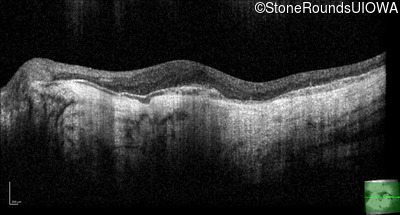

Optical Coherence Tomography - Left - 20/20 -1

Exemplar / OCT Stack

OCT Stack

Infrared Fundus Photograph - Right - 20/100 -2